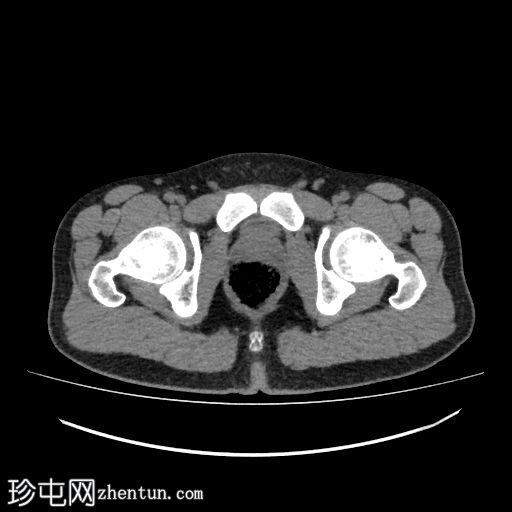

轴位

平扫

4.jpg

右侧输尿管近端至中段在L3-L5椎体水平向内侧移位

输尿管在L3-L4椎体水平轻度节段性隆起

该段输尿管走行于下腔静脉后方,然后从主动脉和下腔静脉之间向内侧走行,远端转向外侧,正常开口于膀胱输尿管连接处

上中段未显影

远端显影的输尿管走行正常,通向膀胱

肾图和膀胱造影正常

无结石

右侧输尿管走行异常,属于环腔静脉/腔后输尿管(2型)